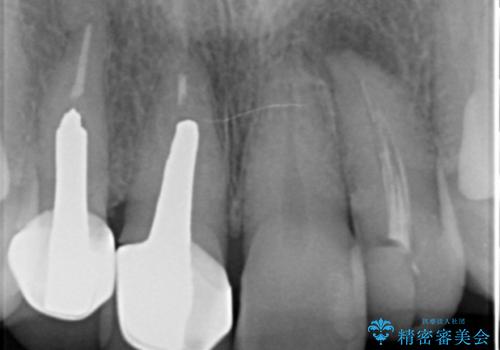

前歯のかぶせもののやり直し、根の治療も

- 前歯のかぶせ物の際が黒いことを気にされて来院。

左上のかぶせ物になっていない歯は根の先に膿がたまっていたので根の治療をし、プラスチックでつぎはぎになっていたためセラミッククラウンでかぶせました。

- 61.6万円 内訳:右上12および左上2(ジルコニアクラウン14万円×3 仮歯1万円×3) 左上2(再根管治療 9万円、ファイバーコア2万円) 費用は治療当時の料金となります

右上12の二本の根の治療は特に行っておらずクラウンのみやり替えを行いました。